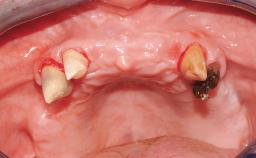

Immediate Loading of Eight Implants in the Maxilla and Six Implants in the Mandible and Final Restoration with Three-Unit and Four-Unit FDPs

Case Type Edentulous Maxilla

Area Full-Arch

# of Teeth All